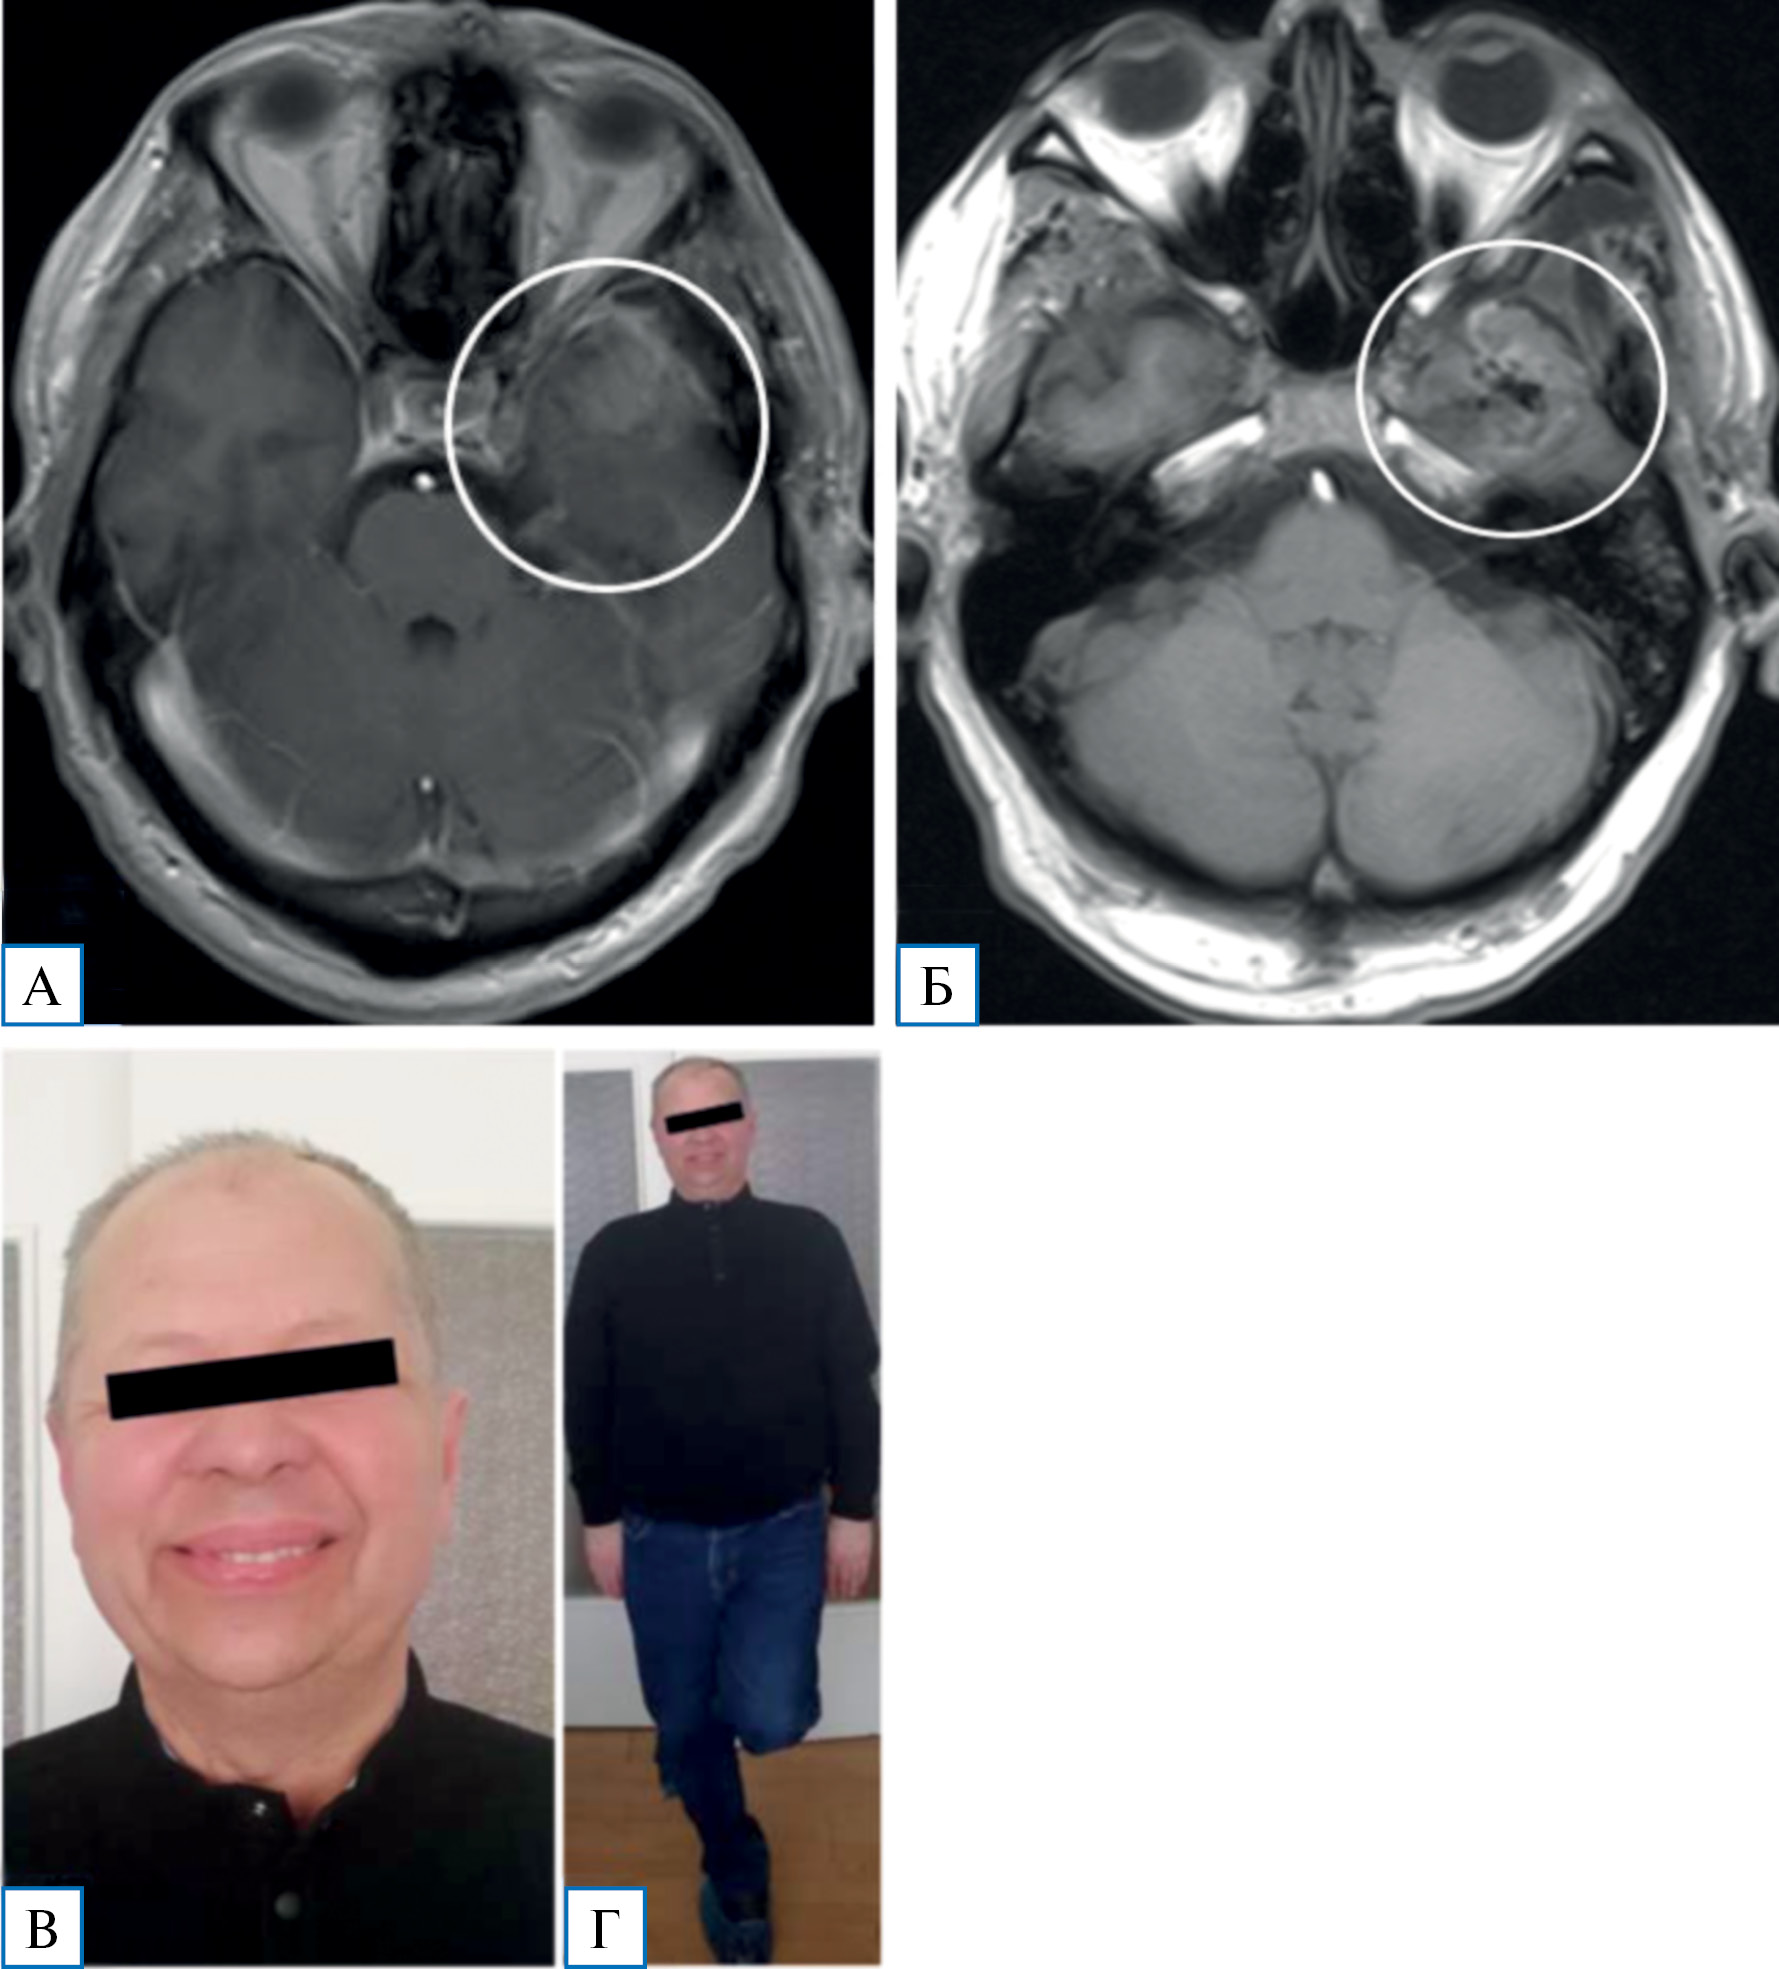

При контрольном осмотре через 1,5 мес после операции состояние пациента удовлетворительное. Жалоб нет. Отмечено восстановление слуха слева. При МРТ головного мозга с контрастным усилением — опухоль удалена тотально, данных за рецидив, наличие гематом не получено; определяется регресс воспалительных изменений в пирамиде левой височной кости (рис. 7).

Рис. 7. Пациент М. после удаления невриномы тройничного нерва, 60 лет

Примечание. А, Б — на снимках МРТ в режиме Т1 минимальные послеоперационные изменения; В, Г — внешний вид пациента через 1,5 мес после операции.